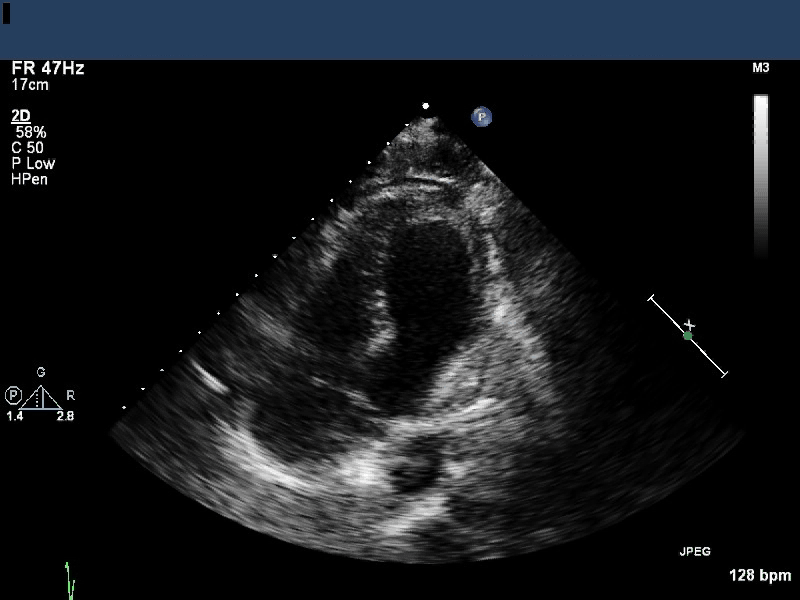

Image 2 is a paraternal long axis. Severe segmental LV dysfunction

with apical akinesis and is again seen. The left ventricular apex

abnormality is less prominently redemonstrated.